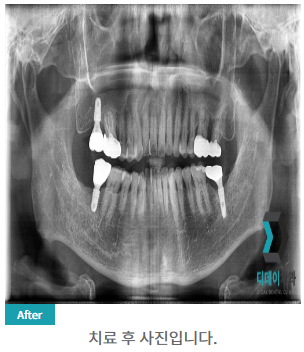

230302

230327

임플란트의 성공 여부는 나이보다는 전신 건강 상태와 구강 상태에 더 큰 영향을 받습니다.

물론 나이가 들수록 뼈의 밀도가 낮아지고 회복 능력이 떨어지는 것은 사실이지만, 이는 개인차가 크고 적절한 처치로 극복할 수 있습니다.

예를 들어, 뼈 밀도가 낮은 경우 뼈 이식술을 병행하여 임플란트의 성공률을 높일 수 있습니다.

| 본 게시물은 의료광고법 제56조 1항을 준수하여, 의료 정보 제공 및 병원 홍보를 목적으로 디데이치과의원에서 직접 작성하였습니다.다만, 블로그에서 제공해 드리는 정보는 참조용으로만 활용하시고, 정확한 개인의 증상 파악은 의료기관에 직접 내방하시어 의료진을 통해 확인하실 것을 권유 드립니다.치과에서 진행되는 모든 시술 및 수술(임플란트 포함)은 개인에 따라 부작용 (염증, 출혈, 부기, 신경 손상 등) 가능성이 있습니다. 따라서 사전에 의료진과 충분한 상담을 통해 결정하시길 바랍니다.게시물의 치료 사진은 실제 본원에서 모든 치료 과정을 마친 환자분의 동의하에 촬영되었습니다. 전후 사진은 동일인이며, 동일 조건하에 촬영되었음을 밝힙니다. |